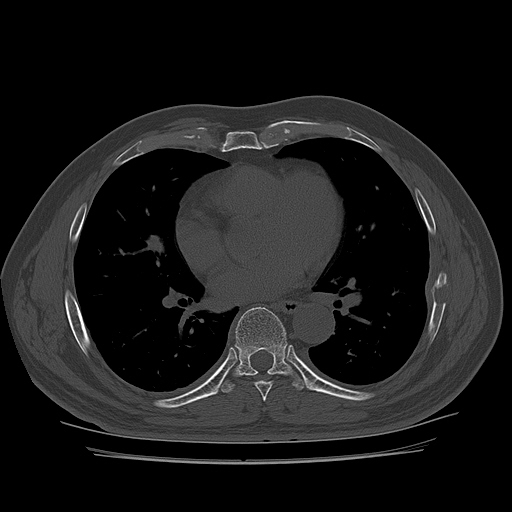

CT ; metastacic mass at rib and adjacent lung

CT image

1893637843_823ab0f0_CT162941144.jpg

1893637843_1a28f778_CT162941145.jpg